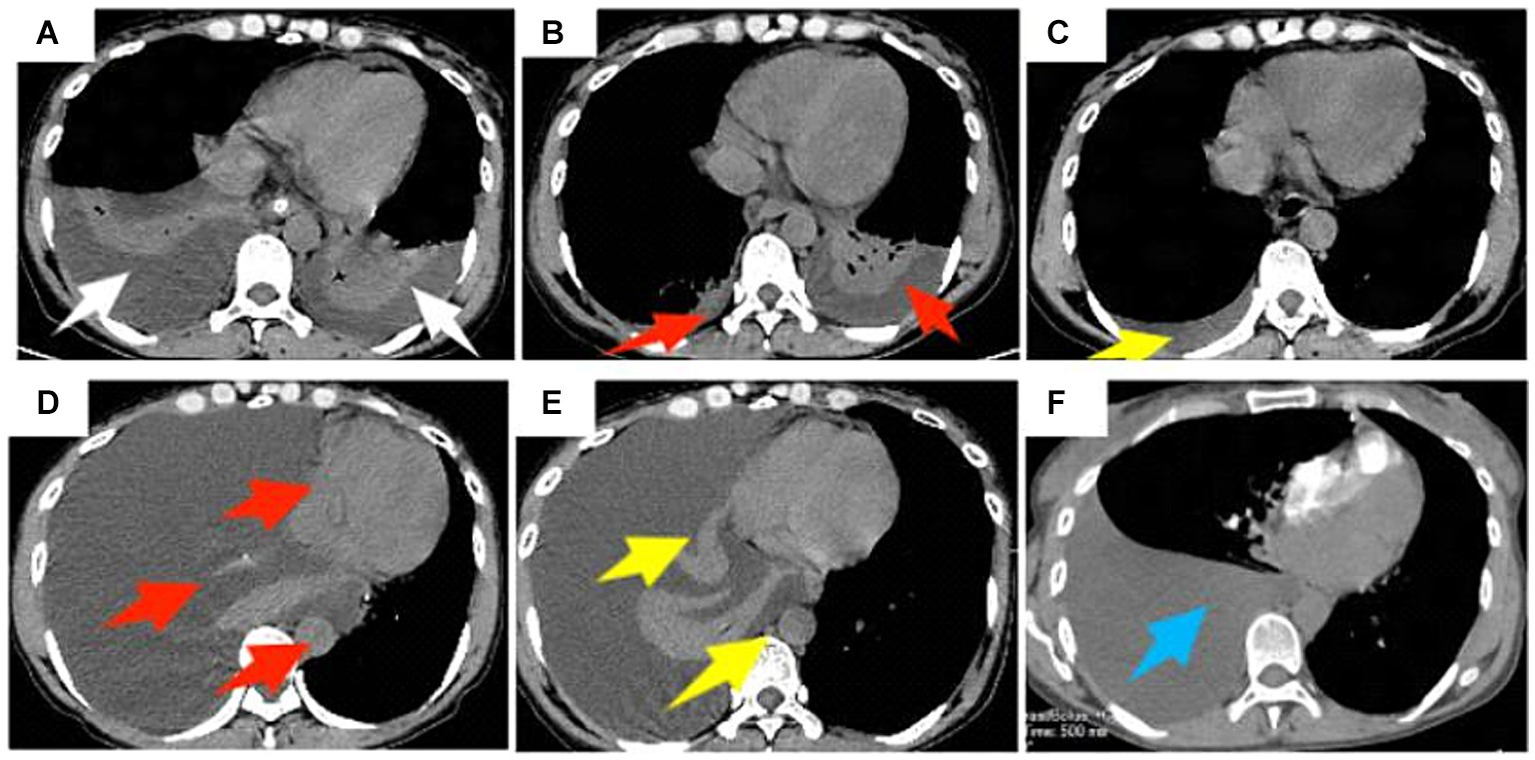

A 47-year-old woman presented for a physical examination with the chief complaint of “Hepatitis C for 10 years and recurrent hematemesis for 6 years.” She had been treated with medication in a local hospital without regular antiviral therapy, and had recurrent symptoms of anorexia and fatigue, without abdominal pain or distension, palpitations, or chest tightness. Her physical examination showed a temperature of 36.5°C, blood pressure at 132/54 mmHg, pulse at 70 beats/min, respiration at 20 beats/min, normal consciousness, a slightly poor mental state, an anemic appearance, no abnormalities on auscultation of heart and lungs, no jaundice, and a soft abdomen without tenderness or rebound tenderness. The spleen was palpable 5 cm below the costal margin, and she had no edema in either leg. She had had hepatitis C for 10 years without other special medical conditions. There were no similar diseases in the family and no family genetic diseases. From 2015 to 2021, she underwent endoscopic ligation and blood transfusion therapy 6 times due to variceal bleeding in the gastric fundus, but the condition still relapsed. On July 23, 2021, she was admitted to the Hepatobiliary Surgery department for treatment based on her medical history and clinical symptoms. According to the 2023 “Endoscopic Diagnosis and Treatment of Esophageal and Gastric Variceal Bleeding: European Society of Gastrointestinal Endoscopy Guidelines” (8), she was diagnosed as having “cirrhosis with gastric fundus varices and hepatitis C cirrhosis” and was admitted for treatment. Upon admission, she underwent relevant examinations, and a gastrointestinal endoscopy revealed severe esophagogastric varices and portal hypertension gastropathy (Figures 1A,B). Plain and contrast-enhanced scans of the upper abdominal vein, hepatic artery, and inferior vena cava revealed the presence of liver cirrhosis (maximum oblique diameter of the right lobe, 10.25 cm; thickness and length of the left lobe, 4.24 cm and 6.12 cm, respectively; thickness of the right lobe, 9.13 cm), splenomegaly (longitudinal diameter and thickness of the spleen, 14.22 cm and 7.98 cm, respectively), portal hypertension (main trunk of the portal vein, 1.58 cm), and splenic varices (Figures 1C,D). Blood routine examination (red blood cell count, 3.66 * 1012/L; hemoglobin, 82 g/L; platelet count, 64 * 109/L), coagulation function (prothrombin time, 13.0 s; international normalized ratio 1.14; activated partial thromboplastin time, 25.7 s; thrombin time, 14.9 s; and thrombinogen quantitative dimer, 0.46 μg/mL) and liver and kidney function tests, and electrolyte and tumor markers were all normal.

Figure 1. Gastroduodenoscopy and computed tomography scan of the upper abdomen in a 47-year-old female patient who had been vomiting blood repeatedly for 6 years before admission. (A,B) Gastroduodenoscopy suggests severe varices of the esophageal and fundal veins (yellow arrows); (C,D) CT scan of the upper abdomen suggests cirrhosis, splenomegaly, and portal hypertension (widening of the main portal vein and varicose splenic veins) (blue arrows).